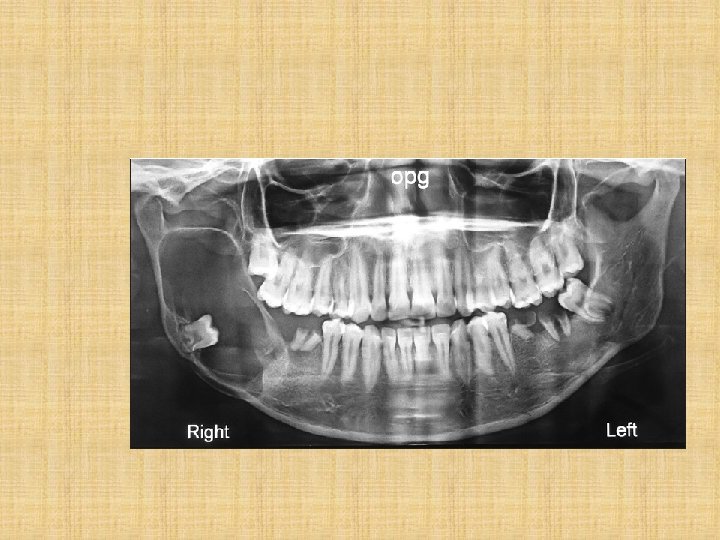

�Nu are tendinta de a invada tesuturile moi �Pe RX apare sub forma de radiotransparenta multiloculara, cu margini neregulate �Apare sub forma de fagure de miere, sau baloane de sapun �Frecvent este prezent un dinte inclus intraosos(M 3 inferior)

Ameloblastomul unichistic �Apare mai ales la pacienti tineri �Se localizeaza de obicei la mandibula, in zona posterioara �Initial asimptomatic, in evolutie poate sa deformeze corticalele osoase, fara parestezia n. dentar inferior �Radiologic apare sub forma unei radiotransparente uniloculare bine delimitate, cu aspectul unui keratochist odontogen

Mixomul odontogen � Rezultatul transformarii tumorale benigne a mezenchimului odontogen � Sunt asemanatoare ameloblastoamelor � Pot aparea la orice varsta, in special intre 15 -30 ani � Sunt fecvente la adolescenti � Se poate localiza oriunde la nivelul maxilarului sau mandibulei � Evolutia este rapida, ducand la erodarea corticalelor � Radiologic, apare ca o radiotransparenta multiloculara sau uniloculara, care impinge radacinile dintilor adiacenti � Formele de mari dimensiuni au aspectul de baloane de sapun